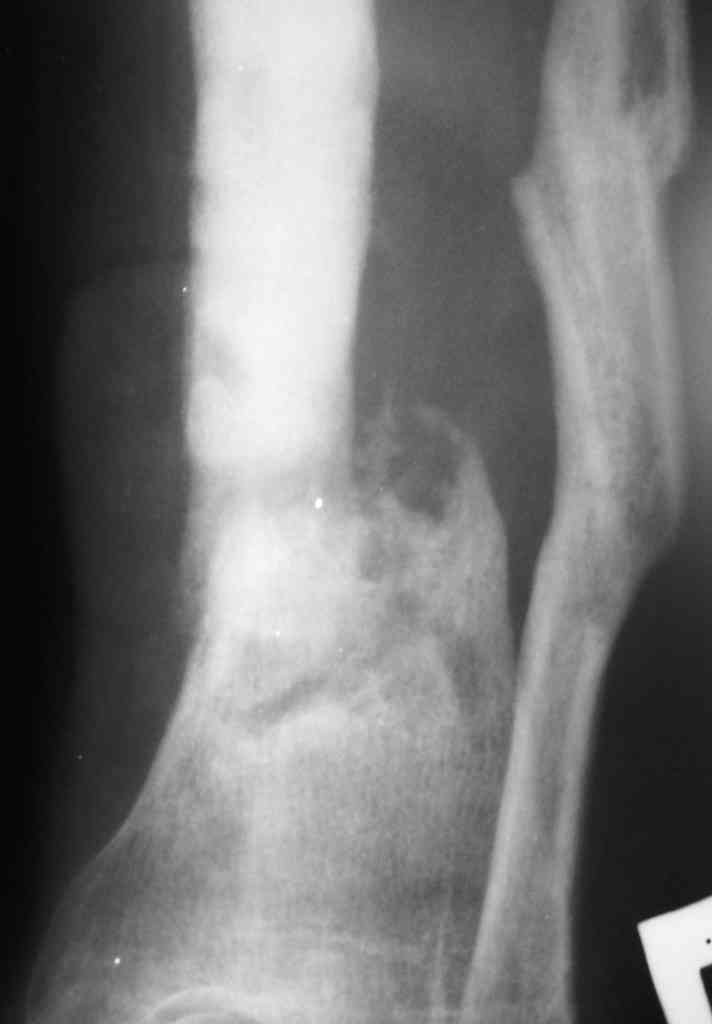

Коротко анамнез: травма в 2004 г. - открытый оскольчатый перелом н/3 голени, имелась рана 4х5 см. по передне-внутренней поверхности. Заживление раны вторичным натяжением. Сращения в АВФ нет. В 2005 г. в нашей клинике произведена костная свободная аутопластика с наложением АВФ. В послеоперационном периоде некроз в области старого рубца 2х3 см., тогда же произведена кожная аутопластика на питающей ножке. Сращения в течение 6 мес. нет, аппарат снят.

В 2006 г. произведена костная аутопластика на сосудистой ножке, иммобилизация гипсовой повязкой. На данный момент признаков консолидации нет.

Периодически у пациента возникают явления дерматита на применение местно лекарственных препаратов на голени, периодически открывается точечный свищ по передней пповерхности в проекции ложного сустава с серозно-гнойным отделянмым.

Укорочение конечности на 4,5-5,0 см., растройств чувствительности нет. При ходьбе конечность нагружает практически полностью при использовании тутора и ортопедической обуви. Внешний вид и R-гр. на фото. У больного еще пока сохранился настрой на лечение.

У меня в мыслях в первую очередь удлинить конечность. В области ложного сустава вмешиваться страшно из-за плохой кожи. Какие будут мысли?